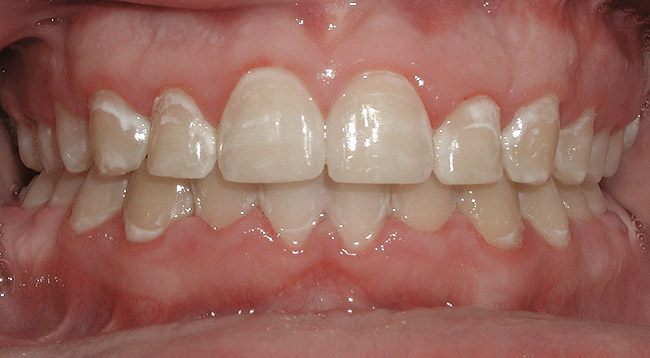

As treatment mechanics and esthetic appliances have improved and treatment times have decreased, orthodontic treatment for adults has risen. Before initiating any prosthetic work, all occlusal issues or esthetic orthodontic concerns should be addressed. Hence, many dentists refer a patient for a complete orthodontic work-up and necessary treatment prior to initiating prosthetic work. Few things are more frustrating for patients than seeing an orthodontist after having a bridge done or implants placed only to learn that their new dental work cannot be moved and, therefore, their malocclusion cannot be fully corrected. In addition, with the aid of low-force and low-friction options that now exist, orthodontists are able to treat periodontally compromised patients who were previously deemed untreatable (Figure 3 and Figure 4). These patients not only are able gain a beautiful esthetic result, but their periodontal health can also be markedly improved.